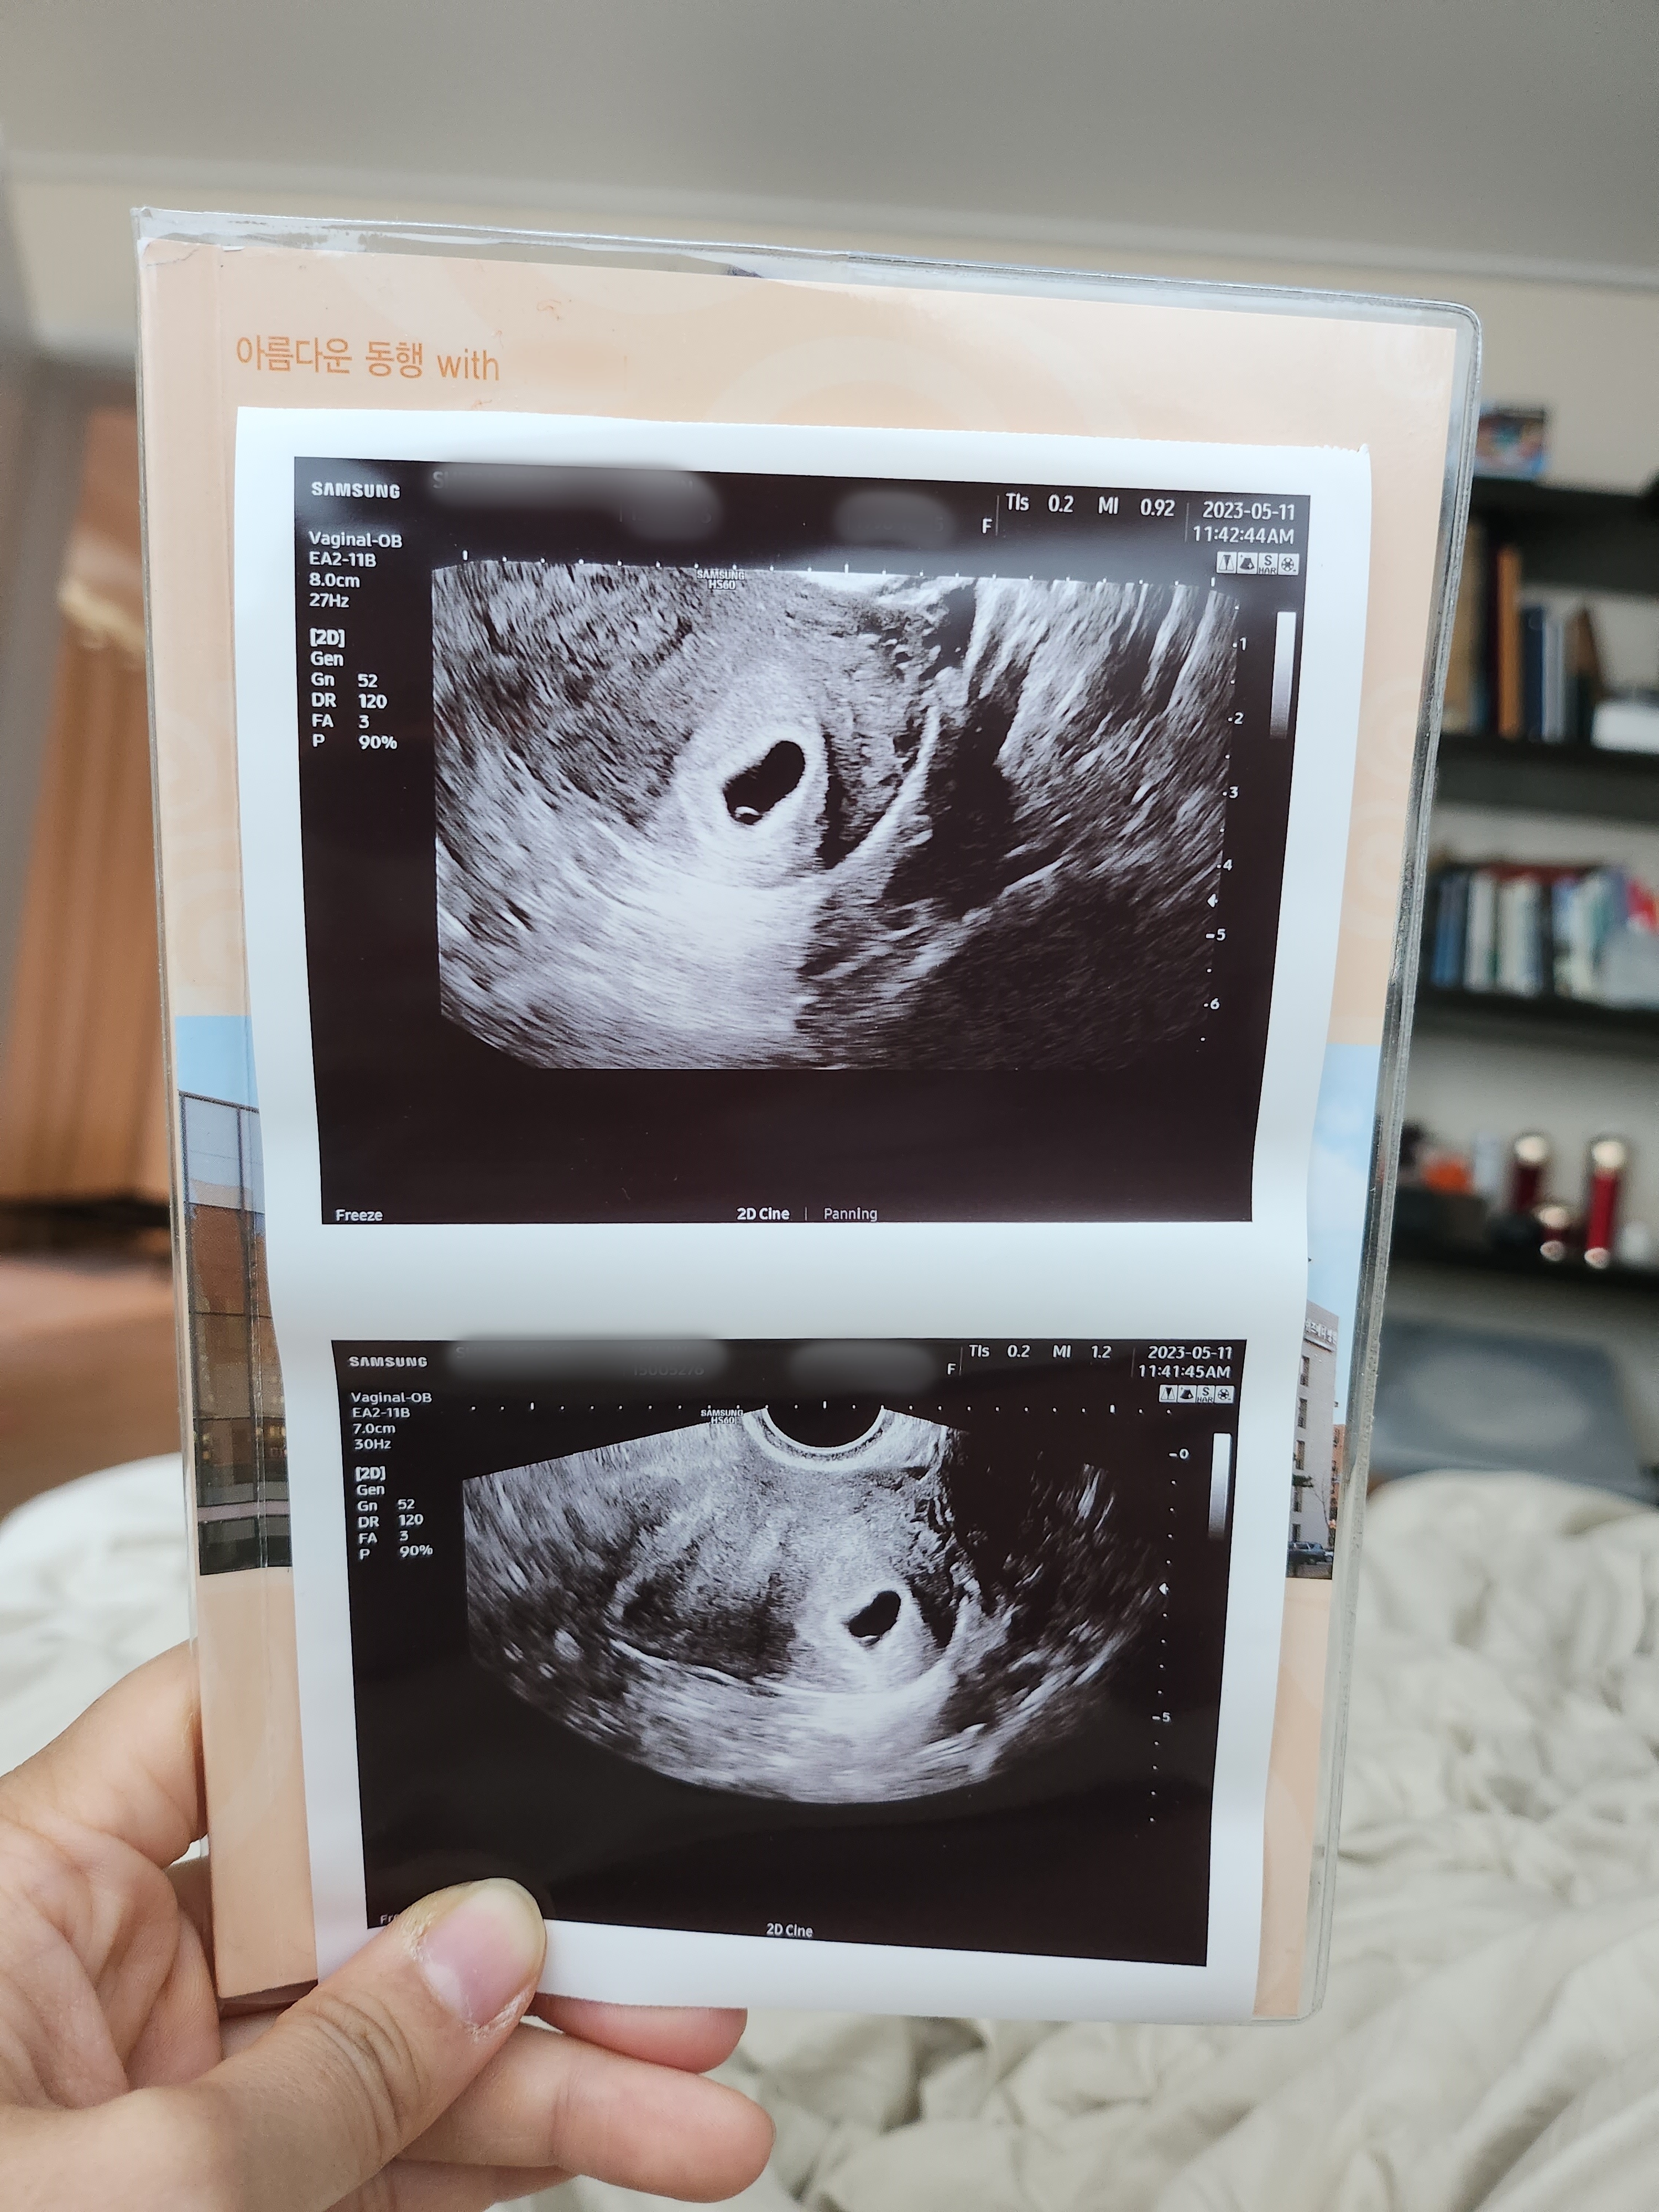

-6주차-

6주0일차에 초음파를 한번 더 보러 다녀왔다.

아기집도 주수에 맞게 잘 커져있고 구석엔 난황도 생겼다고 보여주셨다.

소망이가 너무 잘 크고 있어서 뿌듯하고 좋다.